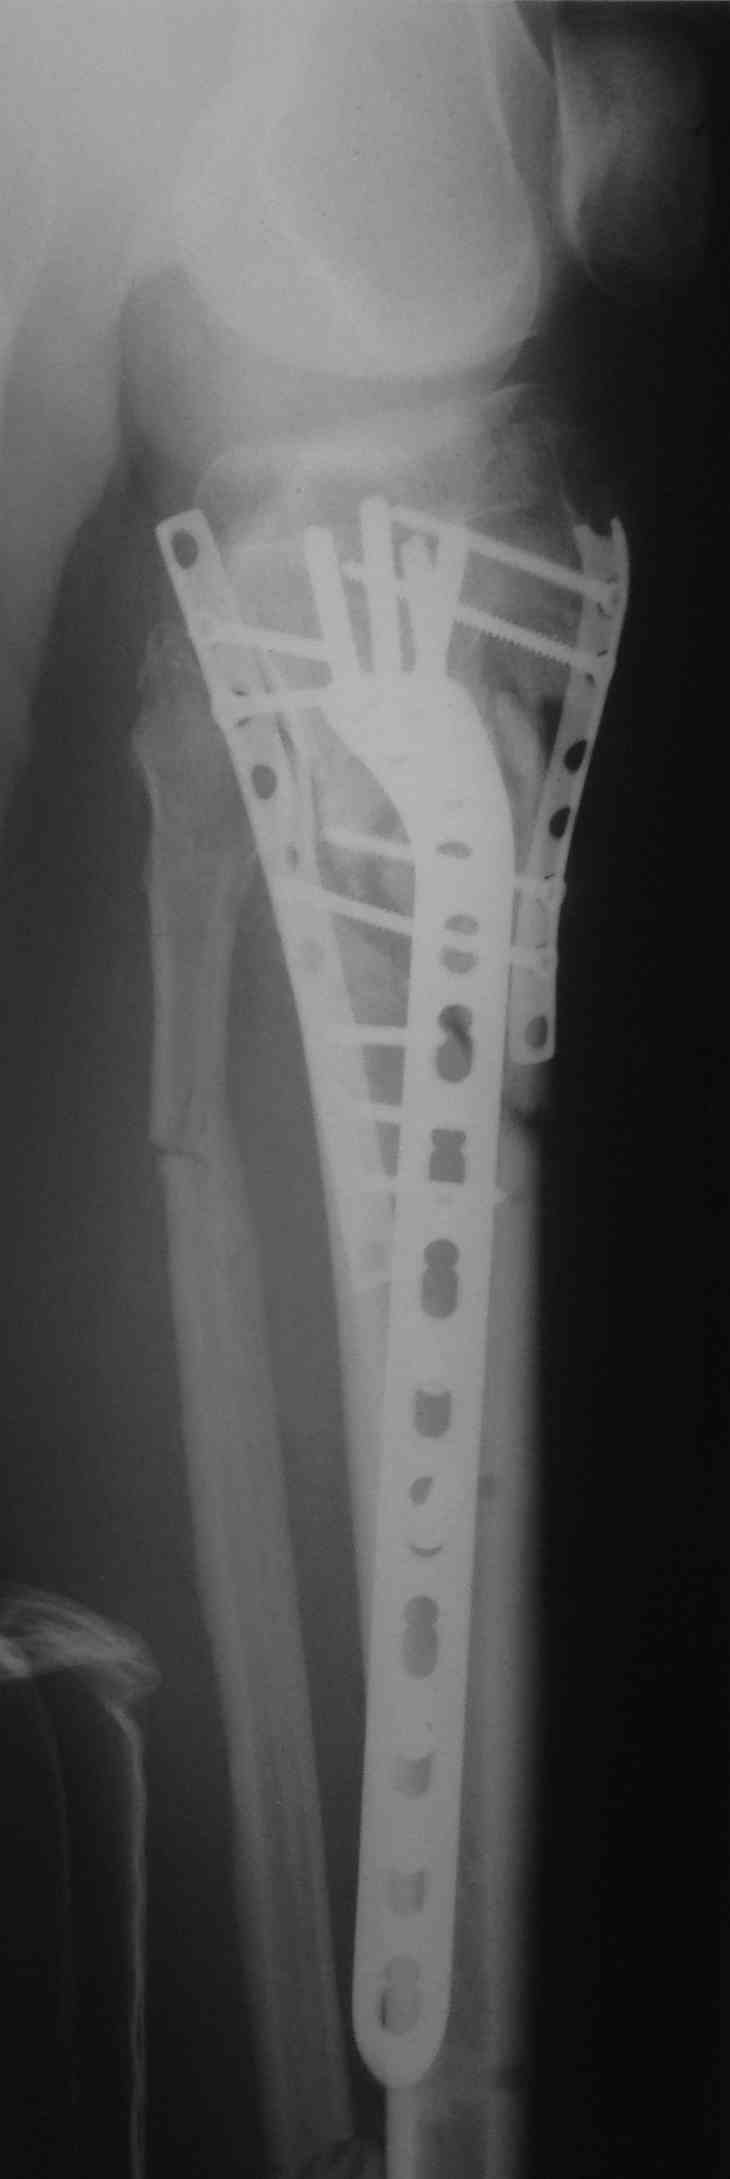

[Ortho] перелом мыщелков голени и вывих бедра (результат операции)

продолжение темы http://weborto.net/forum/1435828753/

Кожа пришла в норму только к полутора месяцам, операция из двух доступов.